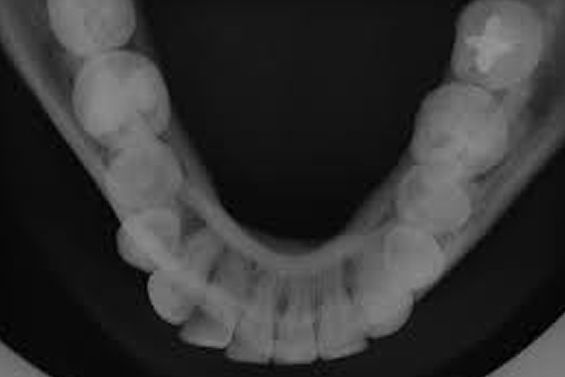

Fotografias Interproximais

Especialmente utilizada para o exame das faces interproximais dos dentes posteriores, com o objetivo de detectar a presença de processos de cáries nesta região, avaliar contorno e adaptação marginal de restaurações e presença de lesões periodontais, auxiliar também nas regiões anteriores para detecção de cárie.